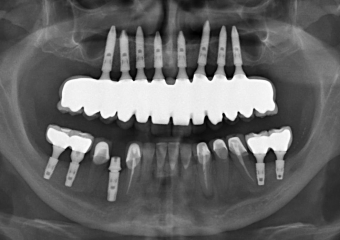

Raio X final com prótese fixa superior em porcelana e zircônia sobre implantes Cone Morse